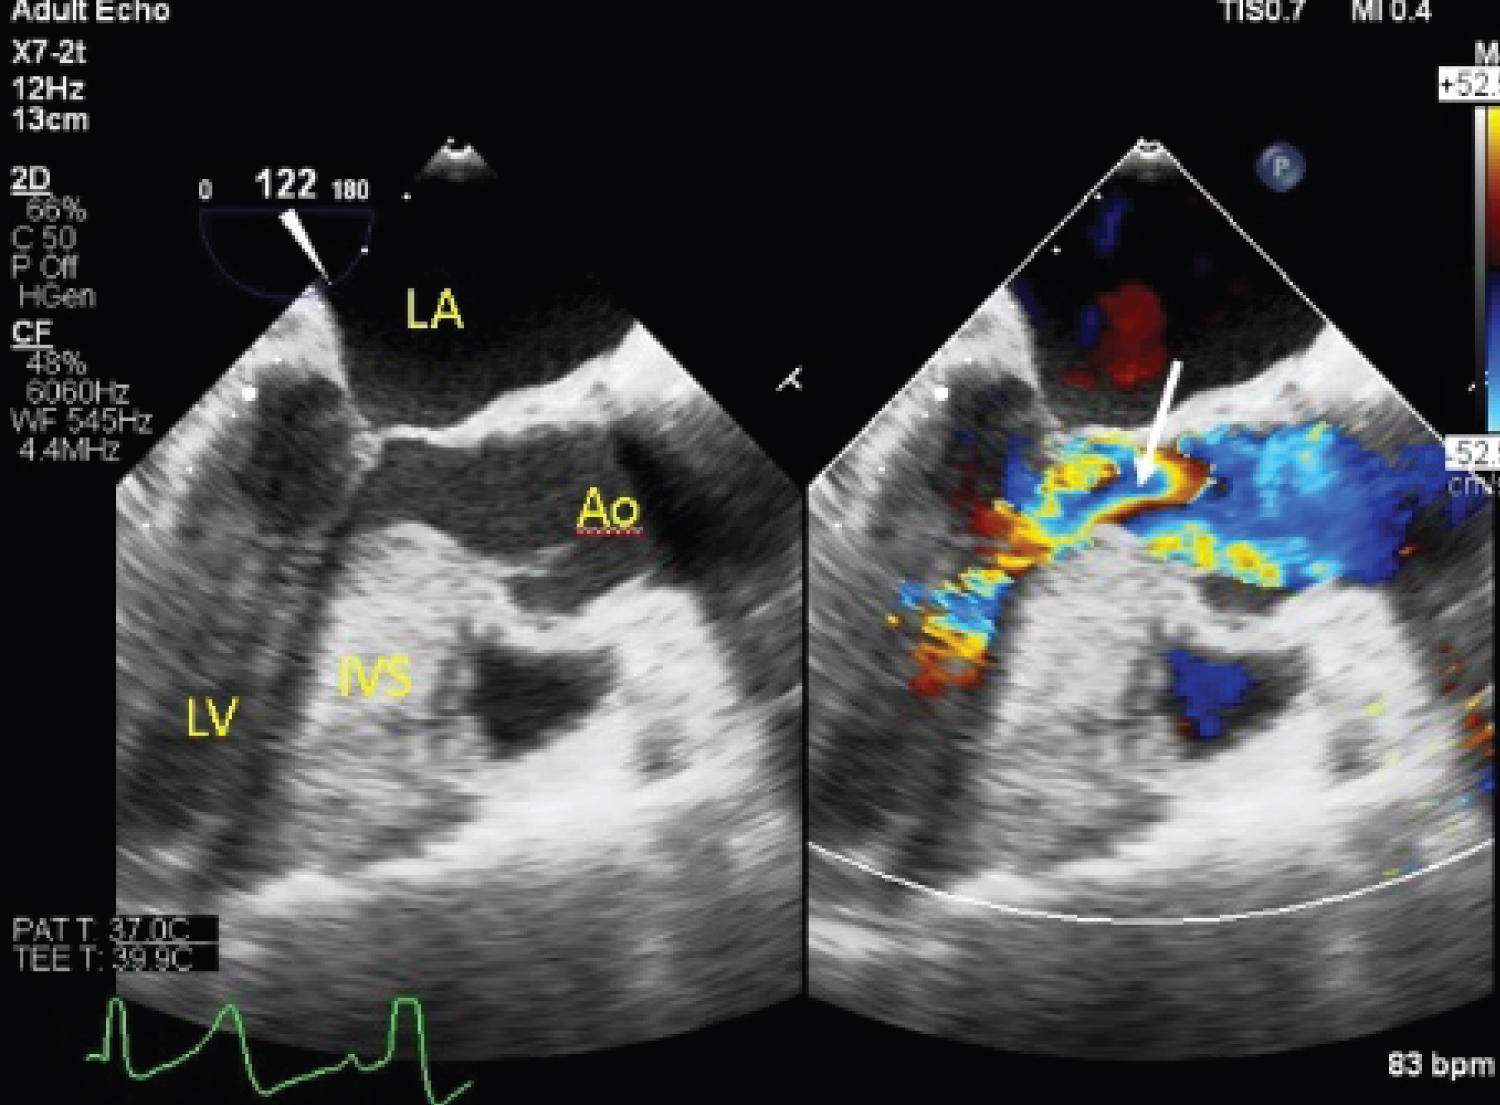

Her case was discussed with the cardiothoracic surgical team, and the decision was for single-vessel coronary artery bypass with left atrial mass excision and mitral valve repair. Intra-operative trans-esophageal echocardiogram showed systolic anterior motion of the mitral valve, with resultant severe mitral regurgitation (Figure 6). The maximum resting intra-left ventricle gradient was measured at 72 mmHg. A well circumscribed mass was attached to the inferior-posterior left atrial wall, in keeping with a known left atrial myxoma. Single vessel coronary artery bypass grafting of the left internal mammary artery (LIMA) to the 2nd diagonal artery with excision of the left atrial myxoma was performed, followed by mitral valve repair with an Alfieri stitch applied from the A2 to P2 mitral leaflets (Figure 7). Immediate post-operative trans-esophageal echocardiogram showed reduction in mitral regurgitation to mild severity with reduction in systolic anterior motion of the mitral valve (Figure 8 and Figure 9). Peak pressure gradient across the left ventricular outflow tract was reduced to 27 mmHg. The patient made an uneventful recovery, and repeat transthoracic echocardiography done on post-operative day 10 showed satisfactory trans-mitral gradient of 3 mmHg with resolution of the prior systolic anterior motion of the mitral valve. There was non-significant left ventricular outflow tract gradient of 28 mmHg at rest. She was discharged the following day.

Figure 8: Post-operative TEE showing reduction in LVOT obstruction (arrow). View Figure 8

Figure 9: Post-operative TEE showing reduction in mitral regurgitation severity (arrow). View Figure 9